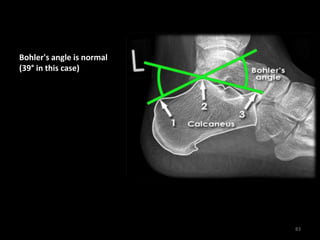

Bohler's angle is normal

(39° in this case)